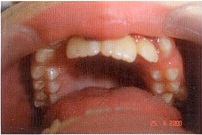

Через три месяца появился прямой контакт в области резцов, подвижность зубов 1.1, 2.1 и 2.2 в пределах нормы. На верхний зубной ряд наложили кантовую NiTi SE 0,016 X 0,022» дугу, сняли окклюзионные накладки. Окклюзионные контакты неплотные. По сагиттали III класс. На повторном ОПТГ и прицельной Rg изменений в области корней верхних резцов не выявлено.

Через 5 месяцев от начала лечения выравнивание верхнего зубного ряда полностью закончено. Зубы 1.1, 2.1, 2.2 заняли правильное положение, получено минимальное резцовое перекрытие около 1—1,5 мм, нормализовалось положение зуба 2.3. Родителям пациента предложено продолжить ортодонтическое лечение на полной несъемной технике для коррекции мезиоокклюзии и нормализации окклюзионных контактов. Согласие родителей получено.